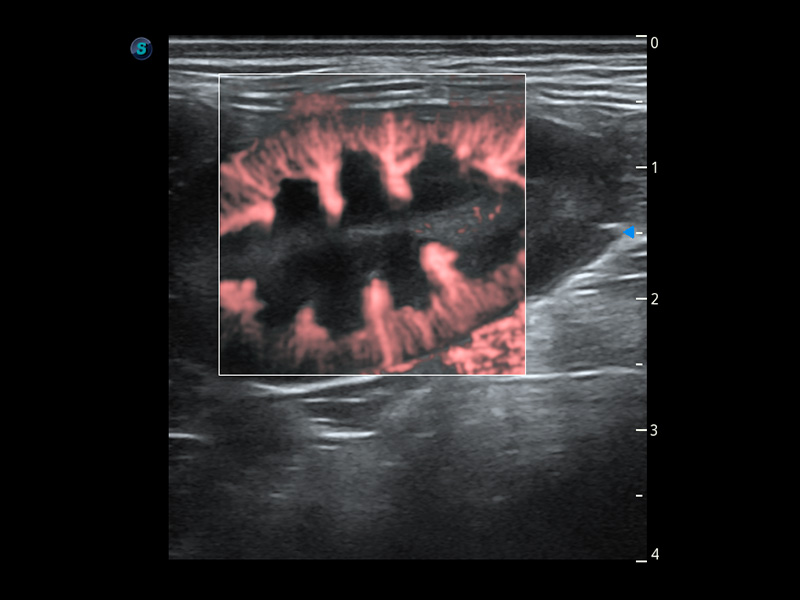

PDI 能量多普勒血流

提供高灵敏度和空间分辦率的血流图像,获得更加真实和丰富的诊断信息。

Bright Flow 立体血流成像

在传统二维血流成像的基础上,呈现血流的立体感,具有动感的生命力之美。精确区分不同血管的空间关系,提高了血流的视觉敏感性。

优异的基础图像

(犬)四腔心血流